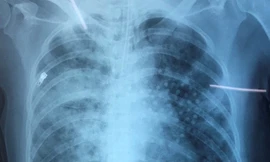

Từ khóa: "viêm phổi hít"

1 kết quả